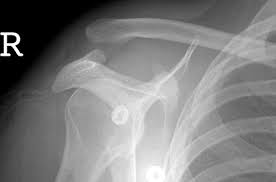

An acromioclavicular joint separation, or ac separation, is a very frequent injury among physically active people.in this injury the clavicle (collar bone) separates from the scapula (shoulder blade). Tears in the ac ligament and the nearby coracoclavicular ligaments, which connect the shoulder blade to the clavicle, cause the collarbone to dislocate. Grade i is slight displacement of the joint, and a badly stretched or partially torn ac ligament. In this case, the collarbone typically angles slightly out of place. Recommended treatment is much like in grades 1 and 2, with a period of immobilization followed by movement to restore shoulder motion and strength.

Tears of the glenoid rim often occur with other shoulder injuries, such as a dislocated shoulder (full or partial dislocation). Tibial spine avulsion acl injury In this case, the collarbone typically angles slightly out of place. It is commonly caused by a fall directly on the point of the shoulder or a direct blow received in a contact sport. Grade ii — the acromioclavicular ligament is completely torn and the coracoclavicular ligament is partially torn. This may take time with a grade 2 ac joint injury. An acromioclavicular joint separation, or ac separation, is a very frequent injury among physically active people.in this injury the clavicle (collar bone) separates from the scapula (shoulder blade). In a grade 3 sprain, the ac joint becomes completely separated. Do not get ahead of yourself. If the ligaments in the ac joint are torn, the condition is more severe (grade 2). Frequently results in a small, permanent bump over the top of the shoulder at the ac joint. Consider shoulder bracing and shoulder ice packs for icing, protecting and resting the deltoid. Although most people think of the shoulder as a single joint between the upper arm bone (humerus) and the torso, the shoulder actually has several smaller joints outside the arm bone's socket.

Do not get ahead of yourself. If the ligaments in the ac joint are torn, the condition is more severe (grade 2). Shoulder ligaments are fibrous bands that hold the bones of the region together and stabilize the shoulder joints. Grade 3 grade 3 acl tears happen when the acl is torn completely in half and is no longer providing any stability to the knee joint. In a severe injury, the ligaments that hold down the collar bone or clavicle are ruptured and the end of the collar bone appears very prominent. A grade 2 injury will involve complete rupture of the acromioclavicular ligament and partial tear of the coracoclavicular ligament. It's unlikely, but you want to make sure there isn't any kind of a break, because if so, you have to keep it immobile until it heals. Types of ac joint injuries.

Brighton and sussex university trust started its physiotherapy led virtual fracture clinic in september 2013. The injury results from a fall onto the point of the shoulder and can be mild, moderate or severe.in a mild or moderate separation, the ligaments involved are stretched. And while performing the deadlift, be sure to place the bar back onto the floor with control — rather than banging it to the floor, since having control is better for the shoulder and back structures. For people with grade 3 ligament injuries usually they can return to work within four weeks. In grade 3 injuries, although the two ligaments are torn and the joint may be significantly disrupted, no attempt is made to reconstruct the ligaments or restore the joint to its normal architecture. A grade 2 separation refers to a rupture of the ac ligament, while a grade 3 separation refers to ruptures of both the ac and the nearby coracoclavicular ligaments. Tears in the ac ligament and the nearby coracoclavicular ligaments, which connect the shoulder blade to the clavicle, cause the collarbone to dislocate. Within one to two weeks most people are able to move their shoulder again without discomfort after suffering from grade 1 or 2 tears, although it can take up to six to eight weeks to return to normal athletic activity. An ac joint injury will either be a minor injury (grade 1 or grade 2), or a major injury (grade 3, grade 4, or grade 5). At the word tear, many envision massive damage and inevitable surgery to repair it or stitch it up.and while surgery is, unfortunately, often the only treatment offered, the truth is, most tendon and ligament tears aren't really extreme enough to require invasive orthopedic surgery as there are nonsurgical interventional. Grade 3 (severe) a complete tear of the ligament resulting in severe pain, extensive bleeding, and swelling. Frequently results in a small, permanent bump over the top of the shoulder at the ac joint. It is commonly caused by a fall directly on the point of the shoulder or a direct blow received in a contact sport.

A grade 2 injury will involve complete rupture of the acromioclavicular ligament and partial tear of the coracoclavicular ligament. It has the normal separation of <4mm. Finding out that you have a torn tendon or ligament can be concerning. Types of ac joint injuries. Recommended treatment is much like in grades 1 and 2, with a period of immobilization followed by movement to restore shoulder motion and strength. Which are not attached to the joint and lie away from the joint. Tearing to ac joint ligaments and other ligaments attached to the collarbone can result in a complete dislocation of the ac joint (grade 3). The athlete is usually unable to bear weight on the limb.

The ac gap is >5mm.